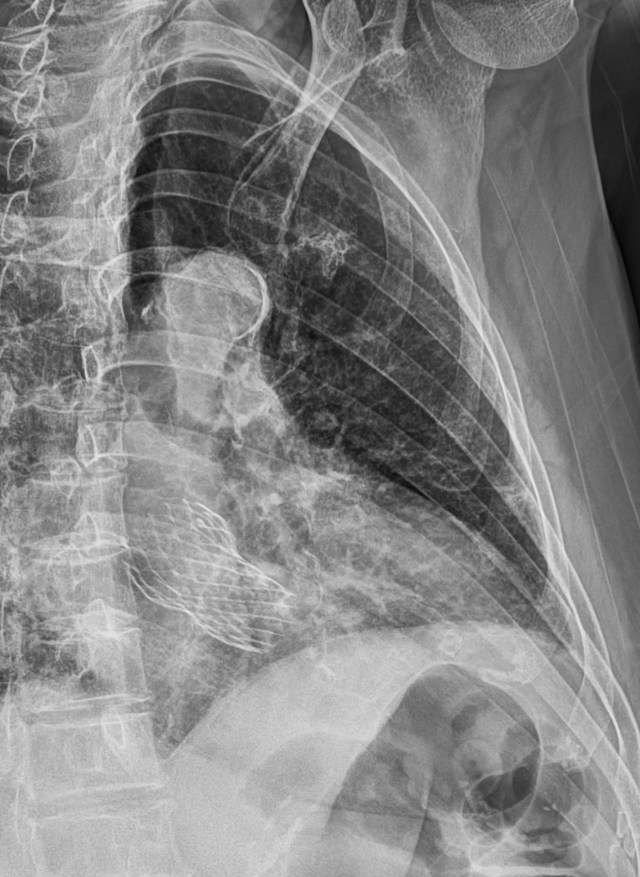

83세 여자환자로 운전 중 교통사고로 앞가슴쪽을 다쳐서 온 환자입니다.

X선영상이나 임상증상이 뚜렷하게 진단을 내리기 어려운 상황이 되자 다음날 흉골의 초음파영상을 의뢰하였습니다.

흉골초음파영상에서는 매우 뚜렷하게 sternum upper body 부위의 transverse fracture와 함께 subperiosteal hemorrhage소견을 보여주었기에 골절을 확진할 수 있었던 사례입니다. 이렇게 뚜렷이 골절소견이 나왔을 뿐 아니라, 조금씩 흉골을 눌렀을 때 위 영상에서와 같이 아랫쪽 bone fragment가 움직이고 있어 불안정 골절임도 알 수 있습니다.

환자가 가장 아프다고 호소했고, 또 멍이 들어있었던 좌측 쇄골하 부위에는 좌측 2-3번 늑골과 costal cartilage가 위치해 있었지만, 늑골이나 늑골연골의 골절소견은 보이지 않았습니다.

특히, 이번 사례에서처럼 환자가 통증을 전혀 다른 곳에서 호소하고 있거나, 육안으로 보이는 멍이 다른 곳에 있는 경우도 존재하므로, 외상환자의 초음파 영상진단 시에는 환자가 호소하지 않는 부위라도 사고 시 발생한 injury mechanism을 고려하여 검사하는 것이 실수를 줄이는 데 유용한 선택이라고 생각합니다.